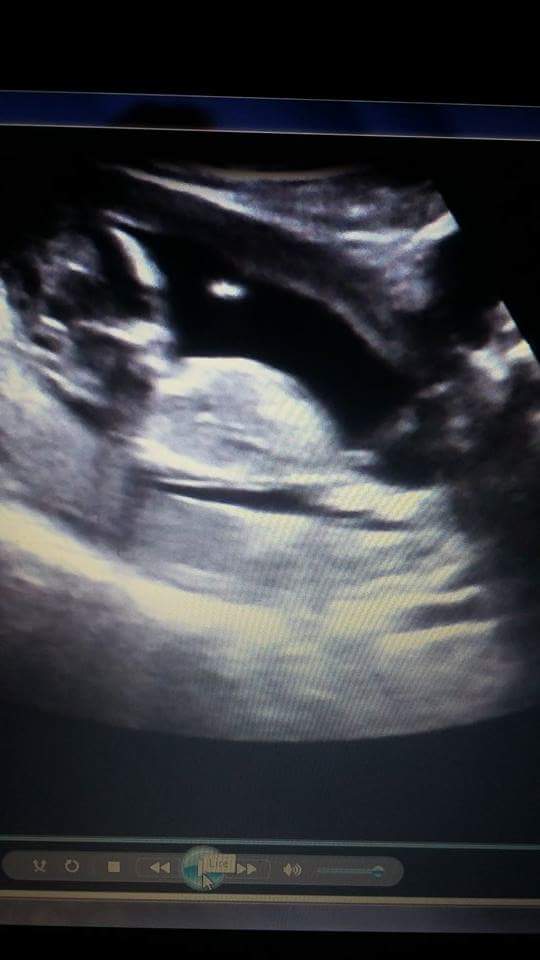

Hi! Can you help me ? I have two pictures. One that shows nub and the other potty shot. Our doctor gave us a guess (boy 70%) but she wasnt sure if it was the cord between the legs or not.